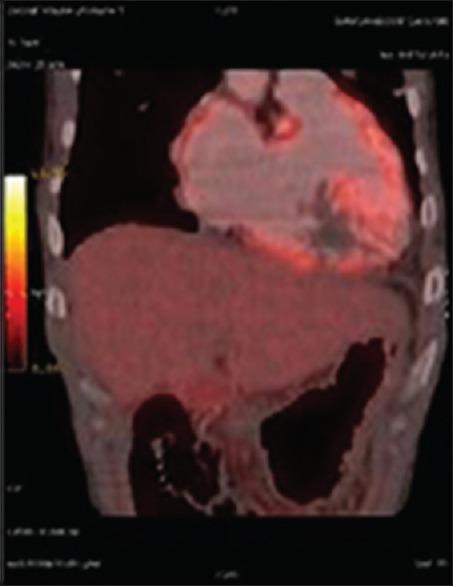

A 36-year-old man with breathlessness and anasarca.

https://cdn.ncbi.nlm.nih.gov/pmc/blobs/16c9/5504903/0f93df6dbdb5/LI-34-395-g001.jpg